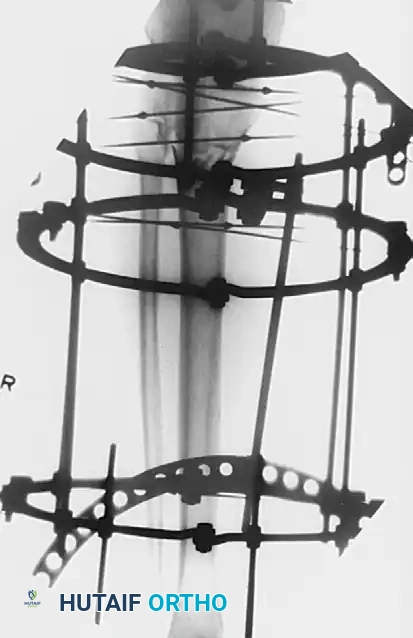

Definitive External Fixation

When soft tissue conditions preclude internal fixation entirely, or in highly contaminated open fractures, definitive treatment with external fixation is indicated. Minimal soft tissue dissection is required, drastically reducing the risk of iatrogenic devascularization and deep infection.

Ring and Wire Fixation (Ilizarov Method):

Clinical studies demonstrate that fine-wire circular fixators yield 87% to 88% good or excellent functional results in complex plateau fractures, with superficial pin tract infections occurring in only 6.5% to 12% of cases. A properly tensioned four-wire construct provides biomechanical stability comparable to dual plating.

In a series of 57 patients with Schatzker type VI fractures treated with Ilizarov fixation (38% of which were open fractures), acceptable reductions yielded an average knee ROM of 115 degrees.

Surgical Warning: Anatomical studies confirm that the knee joint capsule reflects distally up to 14 mm below the articular margin. To prevent the catastrophic complication of septic arthritis tracking from a superficial pin site, all wires and half-pins must be placed strictly extra-capsularly—at least 14 mm distal to the joint line.

Hybrid and Monolateral Fixation:

Monolateral half-pin external fixators or hybrid frames (combining a proximal tensioned wire ring with distal diaphyseal half-pins) offer alternative solutions. These frames are technically less demanding to apply than full Ilizarov frames and allow excellent access for wound care. Accessory percutaneous cancellous screws are frequently utilized in conjunction with the frame to compress and maintain the articular reduction, while the frame neutralizes bending and torsional forces across the metaphyseal-diaphyseal junction.